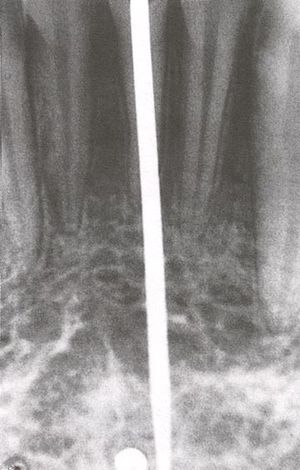

تستعمل سنبلة خاصة أسطوانية لتفريغ العظم بشكل يناسب الغرسة، ويشترط في هذه الطريقة اتباع الأمور التالية:

أن يفرغ العظم بشكل أسطوانة، ويترك العظم في مركز الأسطوانة سليماً وأن ينخفض سطح الغرسة الخارجي عن سطح العظم المغروسة فيه مسافة 5 - 8 مم ولا يجوز بأي حال أن يبرز مهماز الغرسة في منطقةٍ غشاؤها المخاطي متحرك، ويجب أن تكون دائماً في منطقة مغطاة بغشاء مخاطي متقرن.

تكون الغرسة وحيدة الأسطوانة أو ثنائيتها أو ثلاثيتها، وقد جربت هذه الغرسات مدة عام، ثم أجريت دراسة مجهرية على الفك والعظم المحيط بالغرسة، فتبين وجود التصاق كامل بين العظم والسطح المطلي بجزيئات التيتان، كما تبين وجود تشكلات عظمية في الفجوات الموجودة على محيط الأسطوانة المغروسة.